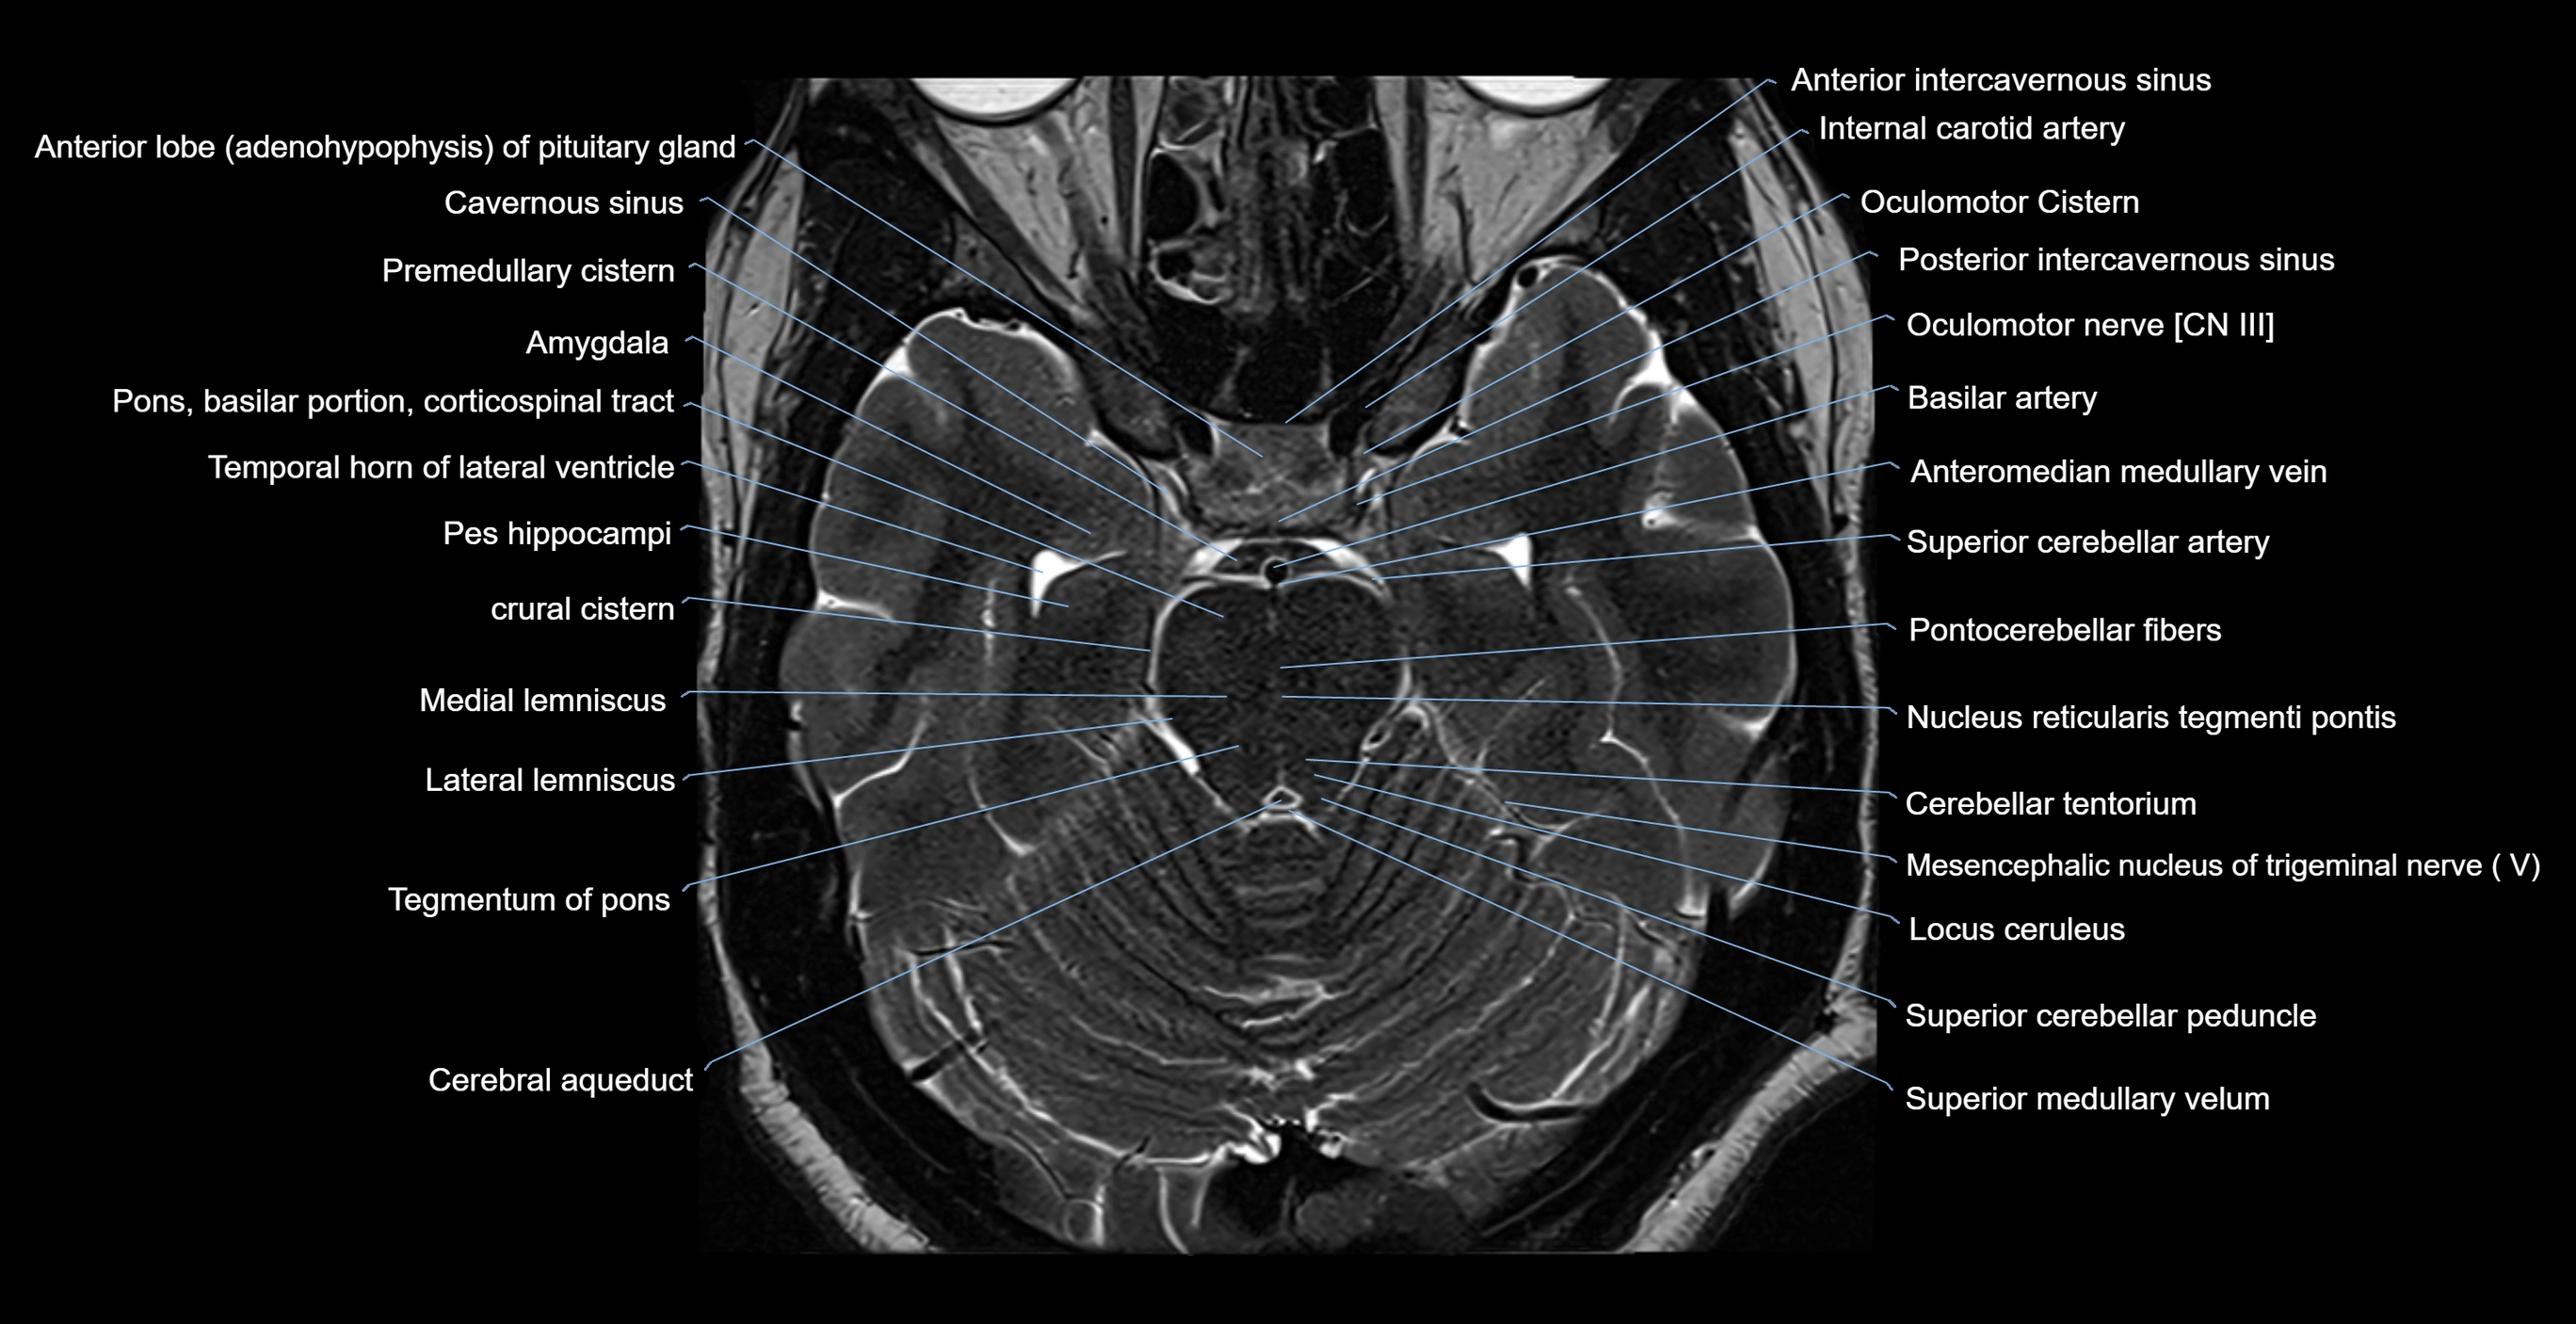

- Amygdala

- Anterior intercavernous sinus

- Anterior lobe of pituitary gland

- Basilar artery

- Cerebral aqueduct

- Crural cistern

- Internal carotid artery

- Lateral lemniscus

- Locus ceruleus

- Medial lemniscus

- Mesencephalic nucleus of trigeminal nerve

- Nucleus reticularis tegmenti pontis

- Oculomotor Nerve (Cranial Nerve III)

- Oculomotor cistern

- Pes hippocampi

- Pons (basilar portion)

- Pontocerebellar fibers

- Posterior intercavernous sinus

- Superior cerebellar artery

- Superior cerebellar peduncle

- Superior medullary velum

- Tegmentum of pons

- Temporal horn of lateral ventricle

- cavernous sinus